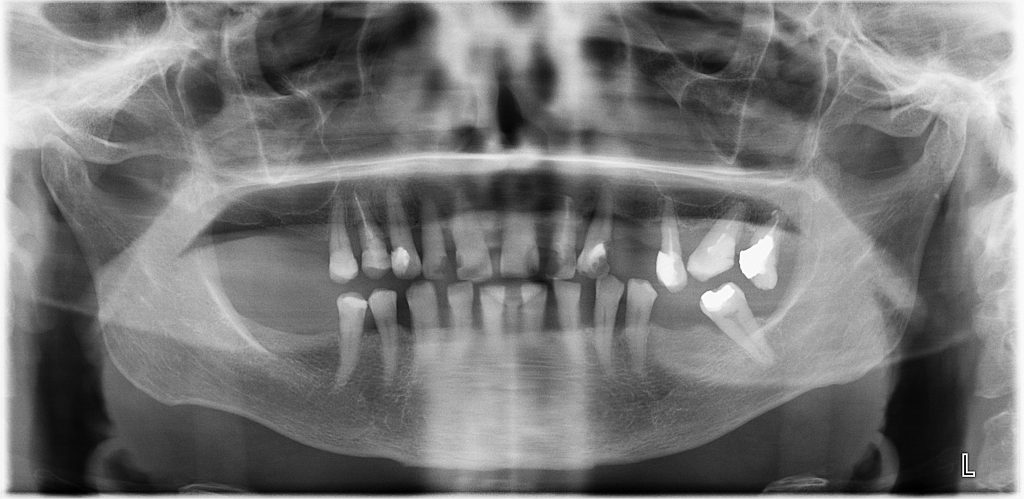

STRESZCZENIE: Uzupełnienie braku pojedynczego zęba w opinii wielu stomatologów nie jest skomplikowane. W takiej sytuacji w pierwszej kolejności przy wyborze sposobu odtworzenia funkcji i estetyki powinno się brać pod uwagę leczenie implantoprotetyczne. Jednakże warunki miejscowe i/lub ogólne bądź względy ekonomiczne często nie pozwalają na wykorzystanie tej metody. W związku z tym nasuwa się pytanie, jakie mamy alternatywy dla korony na wszczepie śródkostnym.

W artykule, na podstawie opisu przypadku klinicznego z nieprawidłowym uzupełnieniem protetycznym, przedstawiono różne sposoby rehabilitacji układu stomatognatycznego oraz ich wady i zalety.